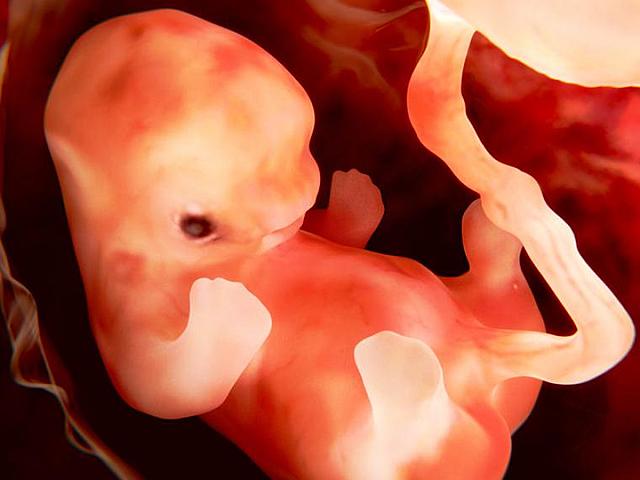

• Semana 5 "El latir del corazón"

Semana 5 "El latir del corazón"

En esta semana los vasos sanguíneos del pequeño ser se desarrollan y es cuando su corazón empieza a latir "algo extraordinario"